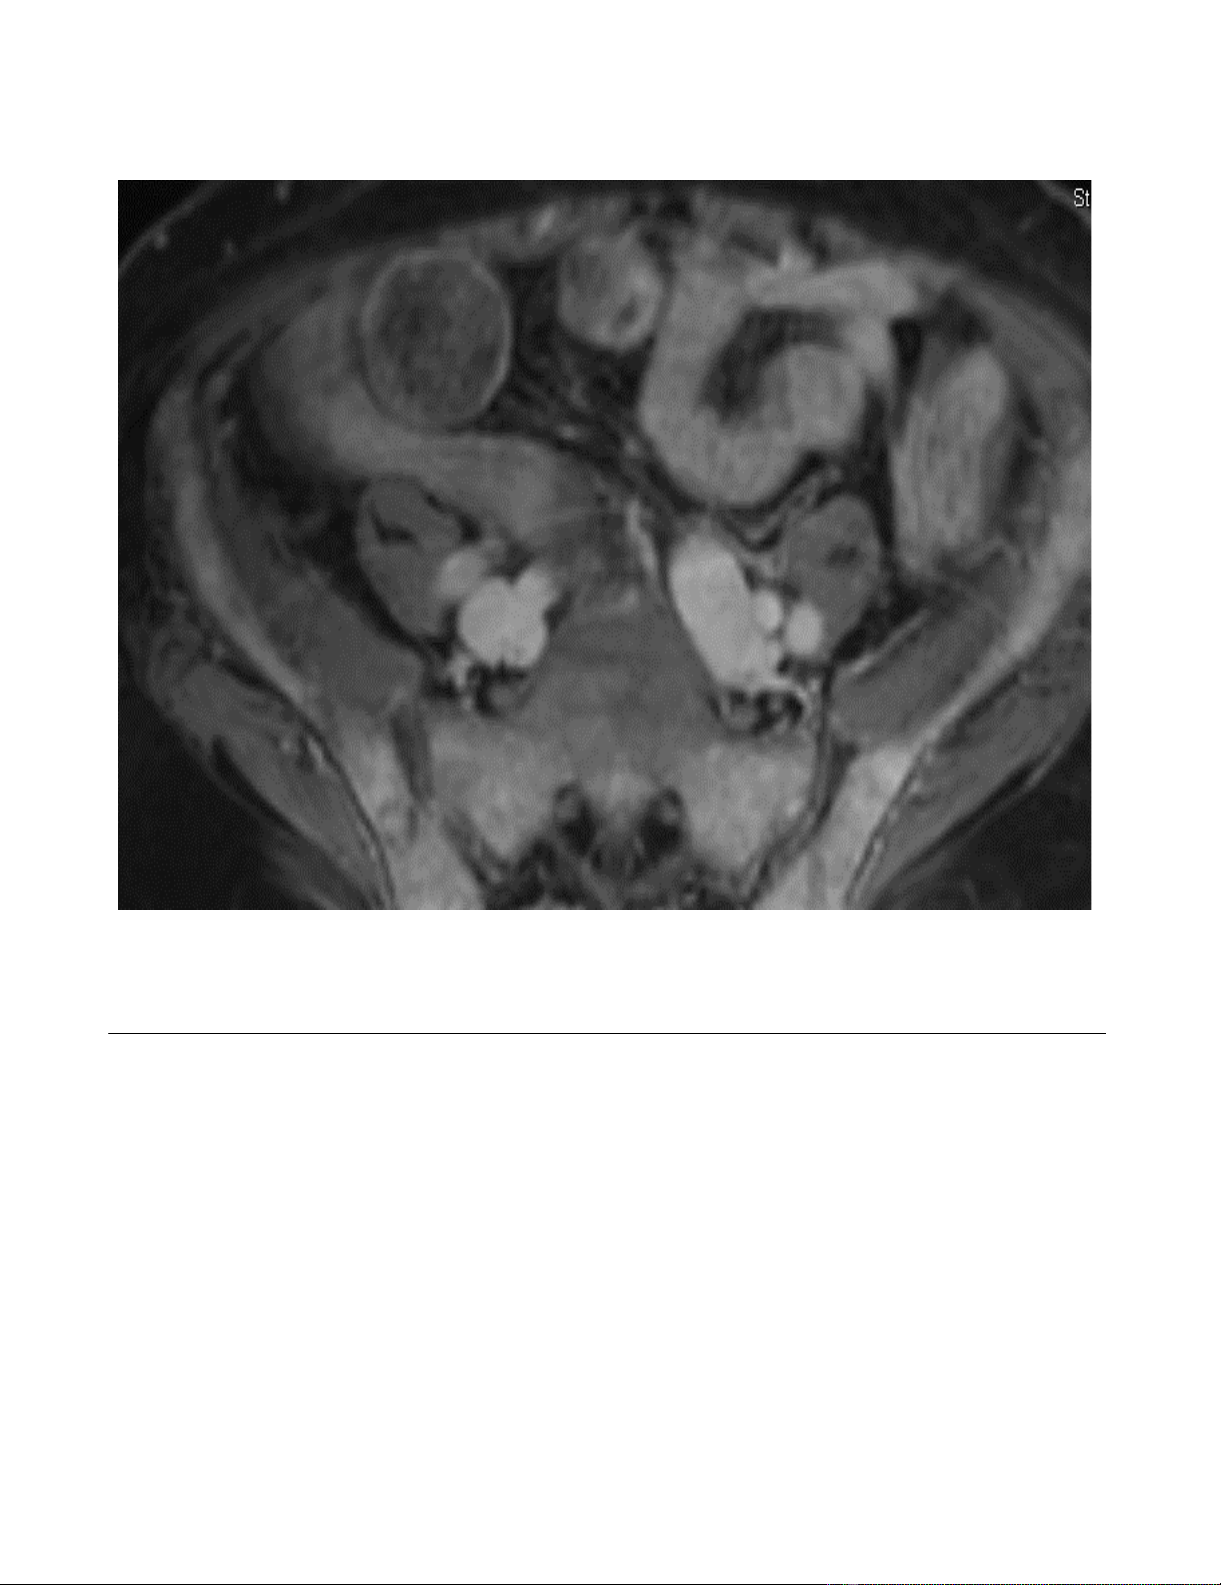

Blood work and magnetic resonance imaging at a recent

out-patient visit demonstrated pancytopenia as well as

diffuse myelomatous bone marrow replacement through-

out his pelvis and proximal femora (Figure 1). At this

MRI pelvisFigure 1

MRI pelvis. Diffuse bone marrow replacement throughout the pelvis and proximal femora with only small areas of residual

fatty marrow in the greater trochanters and femoral heads bilaterally. The diffuse enhancement is consistent with extensive

disease.